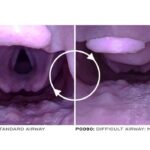

• System pozwala na zmianę modułu dróg oddechowych na wersję z trudnymi drogami oddechowymi (angioedema)